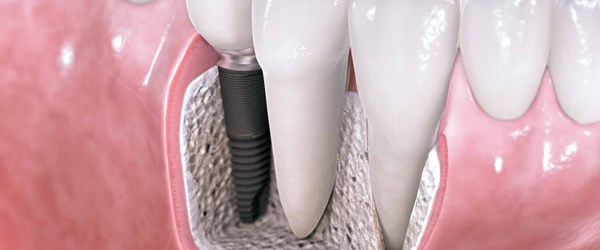

Dental Implants